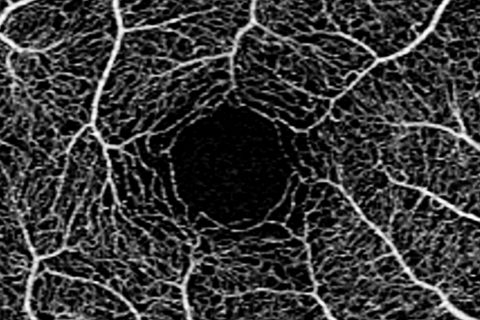

OCT-Αγγειογραφία

Ολοκληρώνοντας τον κύκλο παρουσιάσεων της εκπαιδευτικής ενότητας «Διαγνωστικές εξετάσεις – ερμηνεία και αξιολόγηση», θα συζητήσουμε για την τρίτη κατά σειρά και τελευταία από τις αγγειογραφίες του βυθού και συγκεκριμένα την OCT- αγγειογραφία. Πρόκειται για μια σύγχρονη, μη επεμβατική τεχνική απεικόνισης με συνεχώς εξελισσόμενη τεχνολογία και διευρυνόμενη σειρά ενδείξεων και εφαρμογών, τόσο σε ερευνητικό επίπεδο όσο…